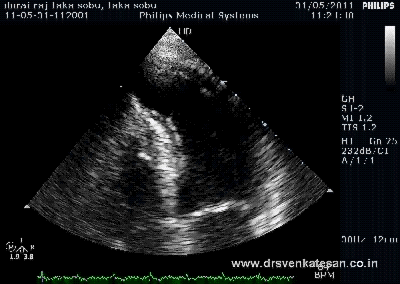

- A meticulous echocardiography

- Hard parameters like pulmonary artery diastolic pressure and pulse pressure